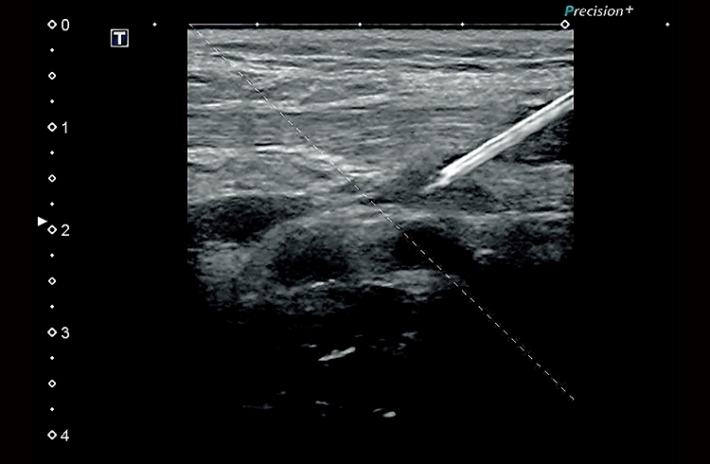

Изображения